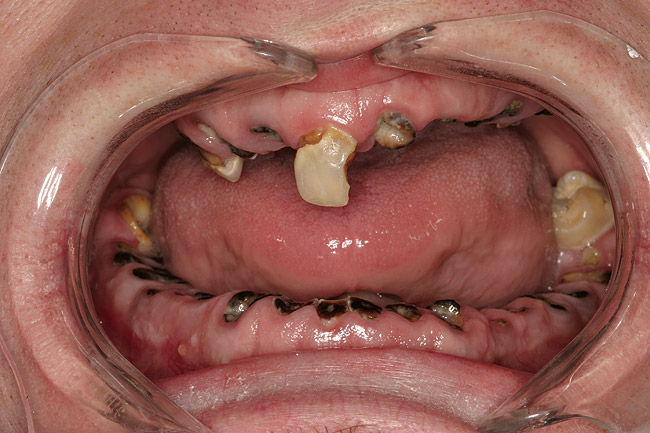

Joe soon learned how to manufacture the drug. His need for meth soon consumed his every thought. He basically lived to do more meth. He admitted that he had made some poor choices. Unfortunately once the addiction kicked in, he no longer had a choice, he had to use. This was his end result (Figure 4 through Figure 6). From these photographs, one might think that he had used the drugs his entire life; however, this progression happened over the course of only about 1 year of smoking the drug. Because of the caustic chemicals (muriatic acid, hydrochloric acid, lithium, etc) his teeth started to blacken, then break.

As a new patient, Joe was instantly likable. He had a great sense of humor. He regretted how his life had turned out. When he finally presented to this author’s practice he was 24 years old. He wanted to remove the evidence of his addiction that were visible to anyone that came in contact with him. His teeth were totally destroyed by his drug use. There was no hope of saving any of them. There were horrible infections in his jaw bones that were spreading through his system. His only option was to remove all of his teeth and have dentures made. Impressions were taken with alginate. A bite was established in maximum intercuspation. We decided that his preoperative incisal edge positions of teeth Nos. 9 and 10 were adequate to recreate the incisal edge position in full dentures.

Figure 5  PRESENTATION CONDITION By the time Joe presented for treatment after serving time in prison and going to rehab, his teeth were completely destroyed by rampant decay. Although some teeth could have been saved, the patient chose to have all of the remaining teeth extracted in order to receive a set of full dentures.

Figure 5

Figure 6  PRESENTATION CONDITION By the time Joe presented for treatment after serving time in prison and going to rehab, his teeth were completely destroyed by rampant decay. Although some teeth could have been saved, the patient chose to have all of the remaining teeth extracted in order to receive a set of full dentures.

Figure 6